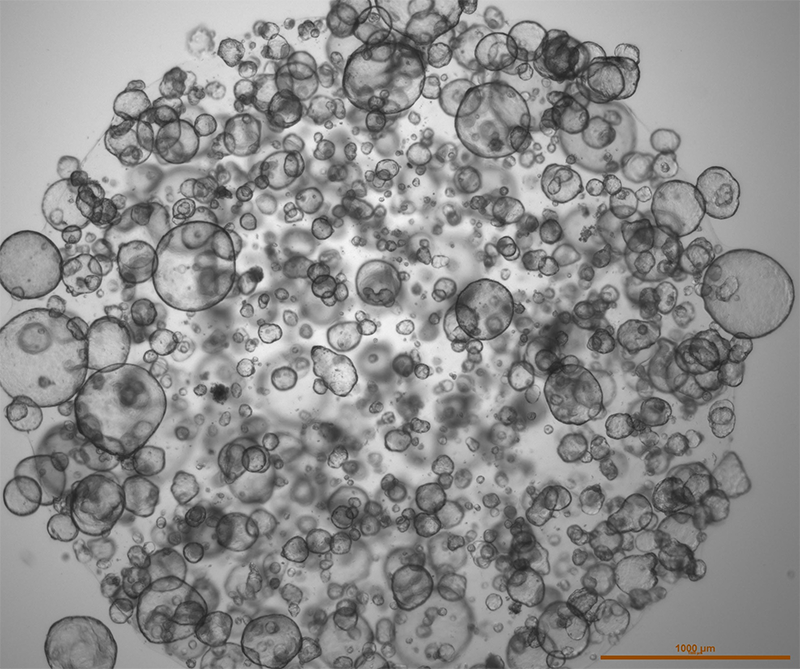

Weiss dreams of having a way to test the regimens before placing people on them. For the past few years, he has been working on making this a reality in collaboration with Tuveson. Their method involves trying the chemo cocktails on pancreatic tumors outside the patient who developed them. In scientific terms such outside tumors are called organoids. They're grown from the small chunks of cancer cells biopsied from patients as part of the diagnosis. Because they retain the characteristics and mutations of the original tumor, their behavior when grown in a lab may predict their behavior inside their human host, including the reaction to the two chemo cocktails oncologists use to treat pancreatic cancer.

Better treatment is where organoids really get their chance to shine. And to some extent they are shining already, as a part of a bigger multi-institute and international effort—a clinical trial called PASS-01, which stands for Pancreatic Adenocarcinoma Signature Stratification for Treatment. When Weiss takes a biopsy, he sends the little cancerous bits to Tuveson’s laboratory where they are grown into organoids in petri dishes. Then, Tuveson’s lab subjects the patient’s organoids to both chemo regimens, noting which one kills cancer more efficiently. Meanwhile, Weiss’s colleagues treat the patient on the chemo regimens. After a while, they compare results and see whether the patients’ tumors and the organoids reacted to treatment the same way. The team hopes to use this clinical trial to show the first scientific proof that organoids can indeed predict how tumors will respond inside the human body.